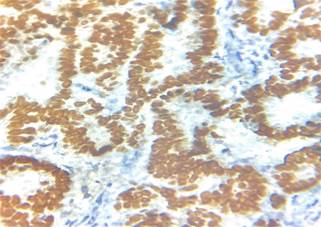

Immunohistochemistry showed diffuse strong

positivity for PAX8 ( Paired Box 8), TTF 1(Transcription Termination

Factor 1), thyroglobulin (Figure 3) and negativity for WT1 (Wilms' tumour gene

1 ) thus confirming the final

diagnosis of papillary thyroid carcinoma in a mature cystic ovarian teratoma.

Figure 3. Immunohistochemistry images showing TTF-1

and thyroglobulin positivity.